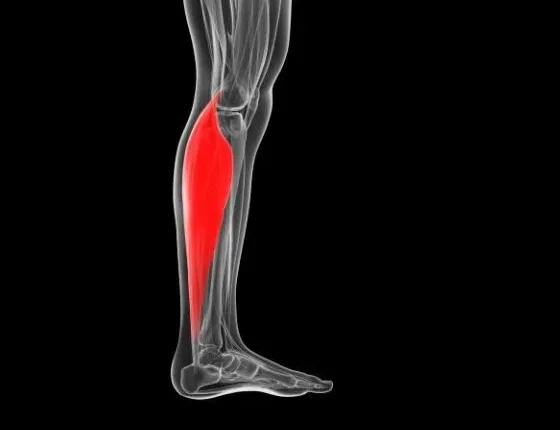

Ο υποκνημίδιος (soleus) ή πελματικός είναι ο μικρότερος επίπεδος μυς που βρίσκεται κάτω από τον γαστροκνήμιο μυ.